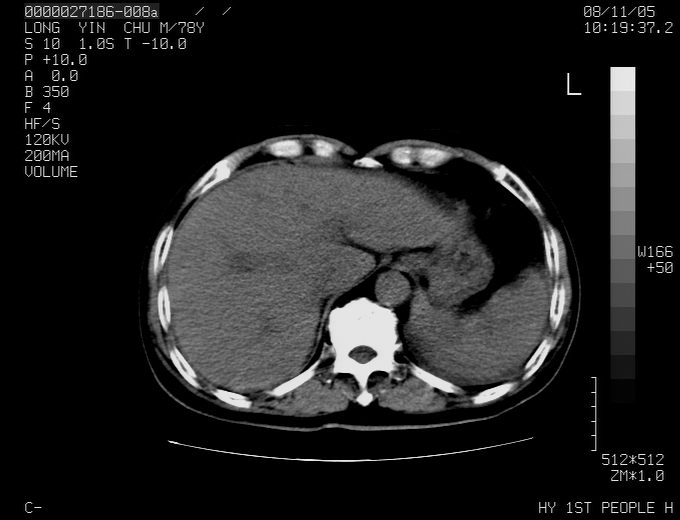

标题: CT16532:M78Y,肝脏病变,请会诊 [打印本页]

标题: CT16532:M78Y,肝脏病变,请会诊

腹胀,腹痛就诊,男性,78岁,外院b超未见异常。

肝ca,脾肾转移

支持脾肾转移瘤,双侧胸腔积液。

考虑弥漫性肝癌并脾及双肾转移.双侧胸水.

图片质量欠佳:多考虑:左侧肾癌。脾脏转移!胸膜转移!

肝脾肾转移瘤可能性大,左肾不除外梗塞,双侧胸水

考虑弥漫性肝癌并脾及双肾转移,双侧胸水。

考虑肝癌并双肾及脾脏转移;双侧胸腔积液。